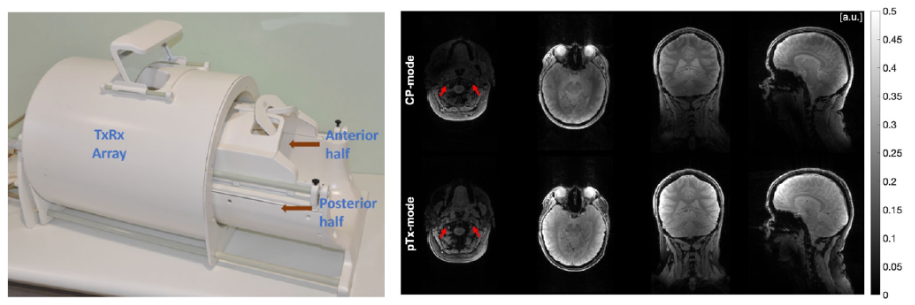

Improving transmit magnetic field homogeneity using a neurovascular head and neck coil with tailored parallel transmission pulses for MRI at 7T

A neurovascular head-and-neck coil (NVHN) [1] provides coverage of the brain and cervical spine enabling neurovascular MRI techniques a 7T. 7T MRI systems improve signal-to-noise ratio and enables faster imaging but capabilities are challenged by non-uniform transmit magnetic fields (B1+). RF pulse design using parallel transmission (pTx) efficiently mitigates B1 + non-uniformity. With a dedicated NVHN coil, RF pulse designs can remain streamlined without the need of coordinating multiple coils imaging different anatomical regions. We demonstrate initial insight using a NVHN coil with tailored pTx pulses to improve signal uniformity across the brain and neck region in vivo.

Scans were performed on a 7T Terra Siemens system using a custom-built 8-transcieve-56-receive NVHN coil. Standard circularly polarised pulses were compared with tailored pTx pulses [2,3,4] to evaluate excitation fidelity across the whole brain and upper neck region using the 3D gradient-recalled echo sequence.

Significant signal uniformity improvements were achieved in the cerebellum, peripheral regions of the head and central neck region in pTx-mode. A median of 22% improvement in excitation fidelity was achieved using pTx pulses across five subjects. This shows promising potential in incorporating pTx pulses in more advanced MRI techniques with targeted interest in both the brain and neck regions.

Figure. Left: 8TxRx56Rx Neurovascular Head-and-Neck (NVHN) coil (Image from [1]). Right: T2*-weighted images acquired with standard pulses in circularly polarised (CP-mode) and with tailored pTx pulses (pTxmode)